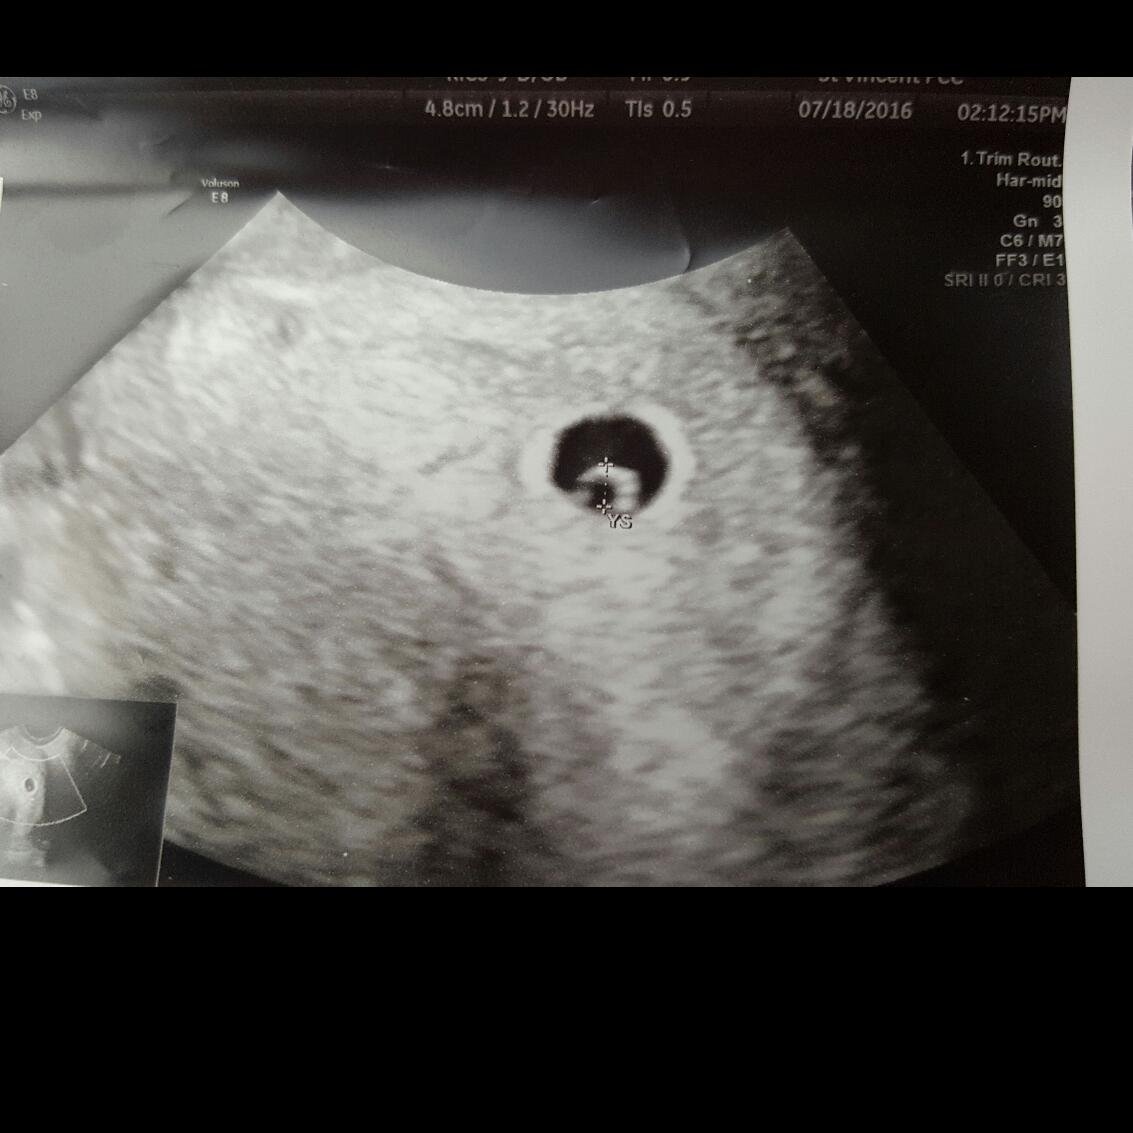

TTC #2: current cycle: 225iu Menopur for 4 weeks, Ovidrel Trigger= BFP! Beta #1; 333, Beta #2 713! 1st u/s showed TWINS (7/18)